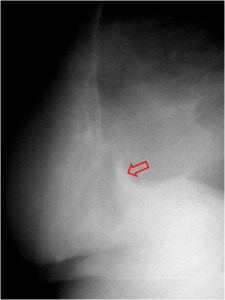

SIGNO DE HOFFMAN-RIGLER

Signo de crecimiento del ventrículo izquierdo en la radiografía lateral de tórax. Consiste en un aumento de la distancia entre la vena cava inferior y el borde cardíaco posterior, mayor de 2 centímetros.

En la imagen vemos el signo en un paciente con insuficiencia aórtica. La flecha roja indica el borde cardíaco posterior y la flecha negra señala la entrada de la vena cava inferior.